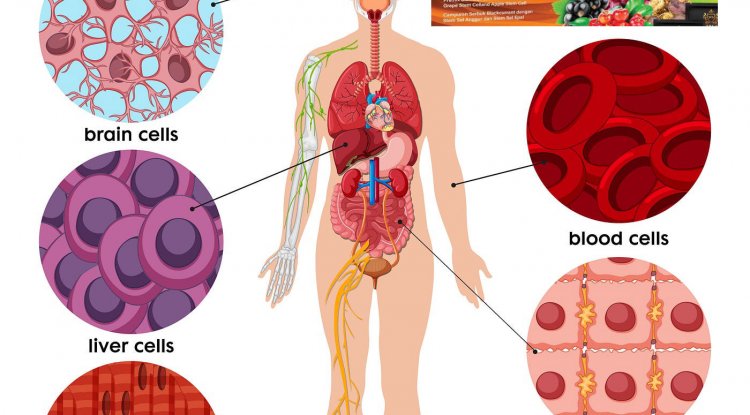

How does the body renew itself with stem cell

How does the body renew itself? How do cancer cells use the same or similar processes to form tumors and spread throughout the body?...

What is Stem Cell

A cell that can divide to form more stem cells as well as giving rise to specialized cells (blood cells, nerve cells, muscle cells,...